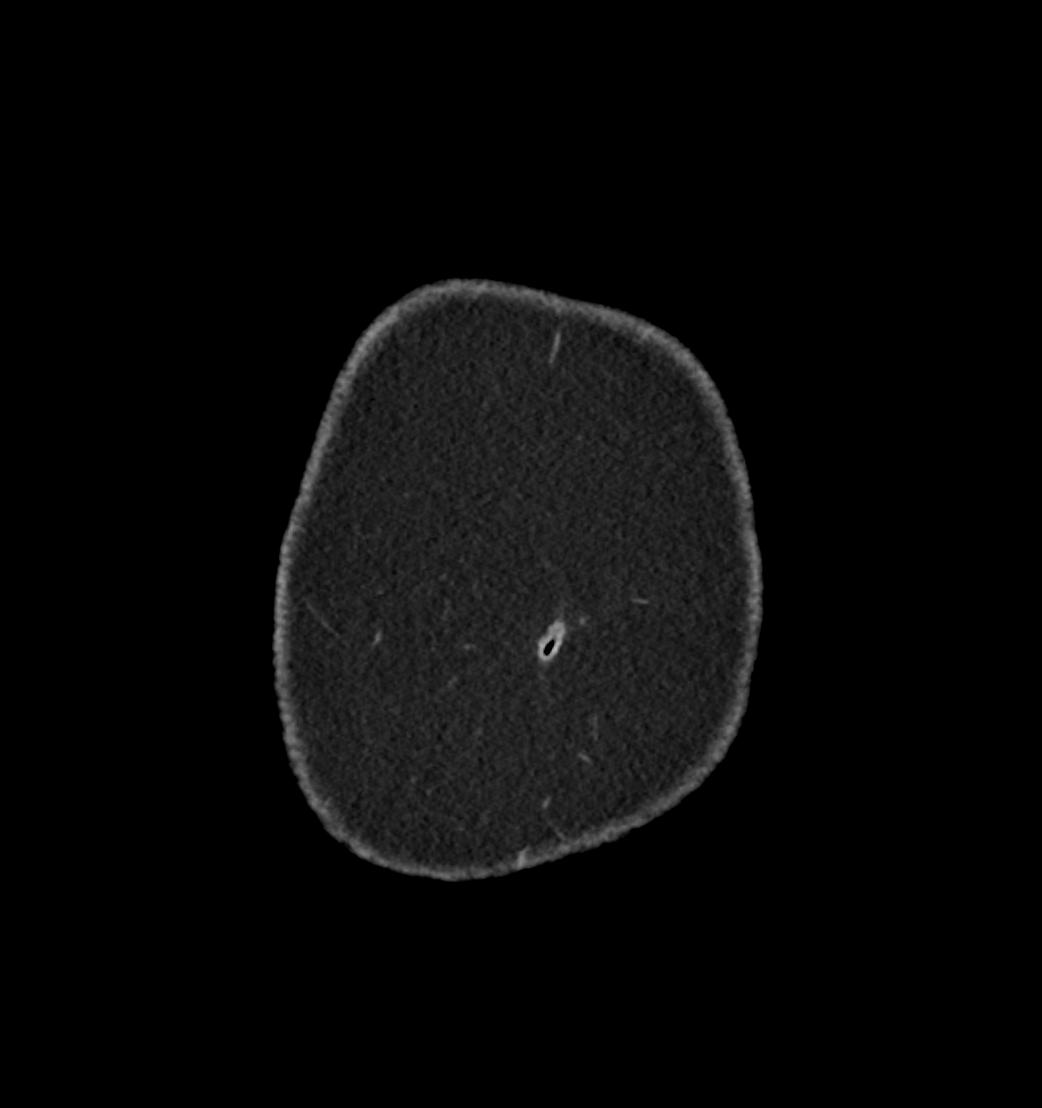

Patient: Padmakumar A. , *1988-04-24, PID: 3000069741773230809

Study Description: CT ABDOMEN

Image Series: Abdomen Cor 3mm [4]

<< Previous | Image 8 of 119 | Next >>